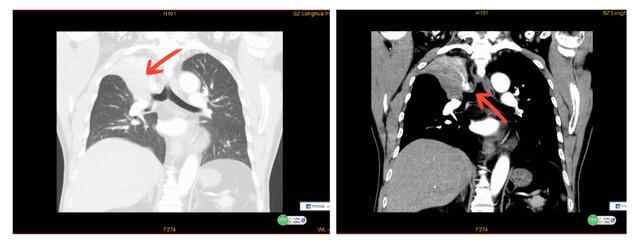

62岁的朱先生咳嗽伴气促已有4年,近6个月病情加重。20多天前,在龙华区人民医院呼吸与危重症医学科经支气管镜检查并活检,确诊为小细胞肺癌。

呼吸内科主任沈观乐建议,可以采用经支气管冷冻消融术治疗。据悉,这是一项处理肺癌病变的新技术。手术当天下午麻醉科主治医师谢凌峰麻醉成功后,沈观乐在余瑞林副主任医师配合下,顺利插入硬质支气管镜,再通过软镜下置入一次性软性冷冻消融针,到达病灶部位进行消融,过程顺利。